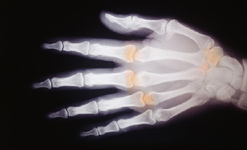

Aching joints and creaking bones are typical symptoms of arthritis. Perhaps for this reason, it’s often thought of as an old person’s disease. But it’s a condition that affects all ages. Toddlers suffer from arthritis-induced early morning stiffness. Teenagers may have to wear splints.

There are hundreds of different types of arthritis. Many of the drug treatments have side effects and each individual reacts differently.